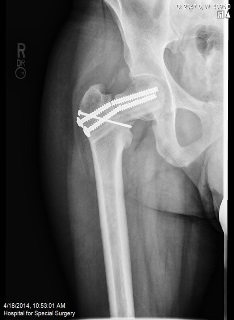

A 37-year-old athletic male underwent an open reduction and internal fixation (ORIF) of his right hip for a stress fracture sustained whilst running the New York Marathon. However, due to non-union of his fracture he underwent revision of the fixation with bone grafting. He presented with persistent pain in the right hip after 18 months from his second operation.

Plain radiographs were performed.

Q. What are your thoughts on the findings of the above radiographs?

The radiographs show non-union of the hip fractures.